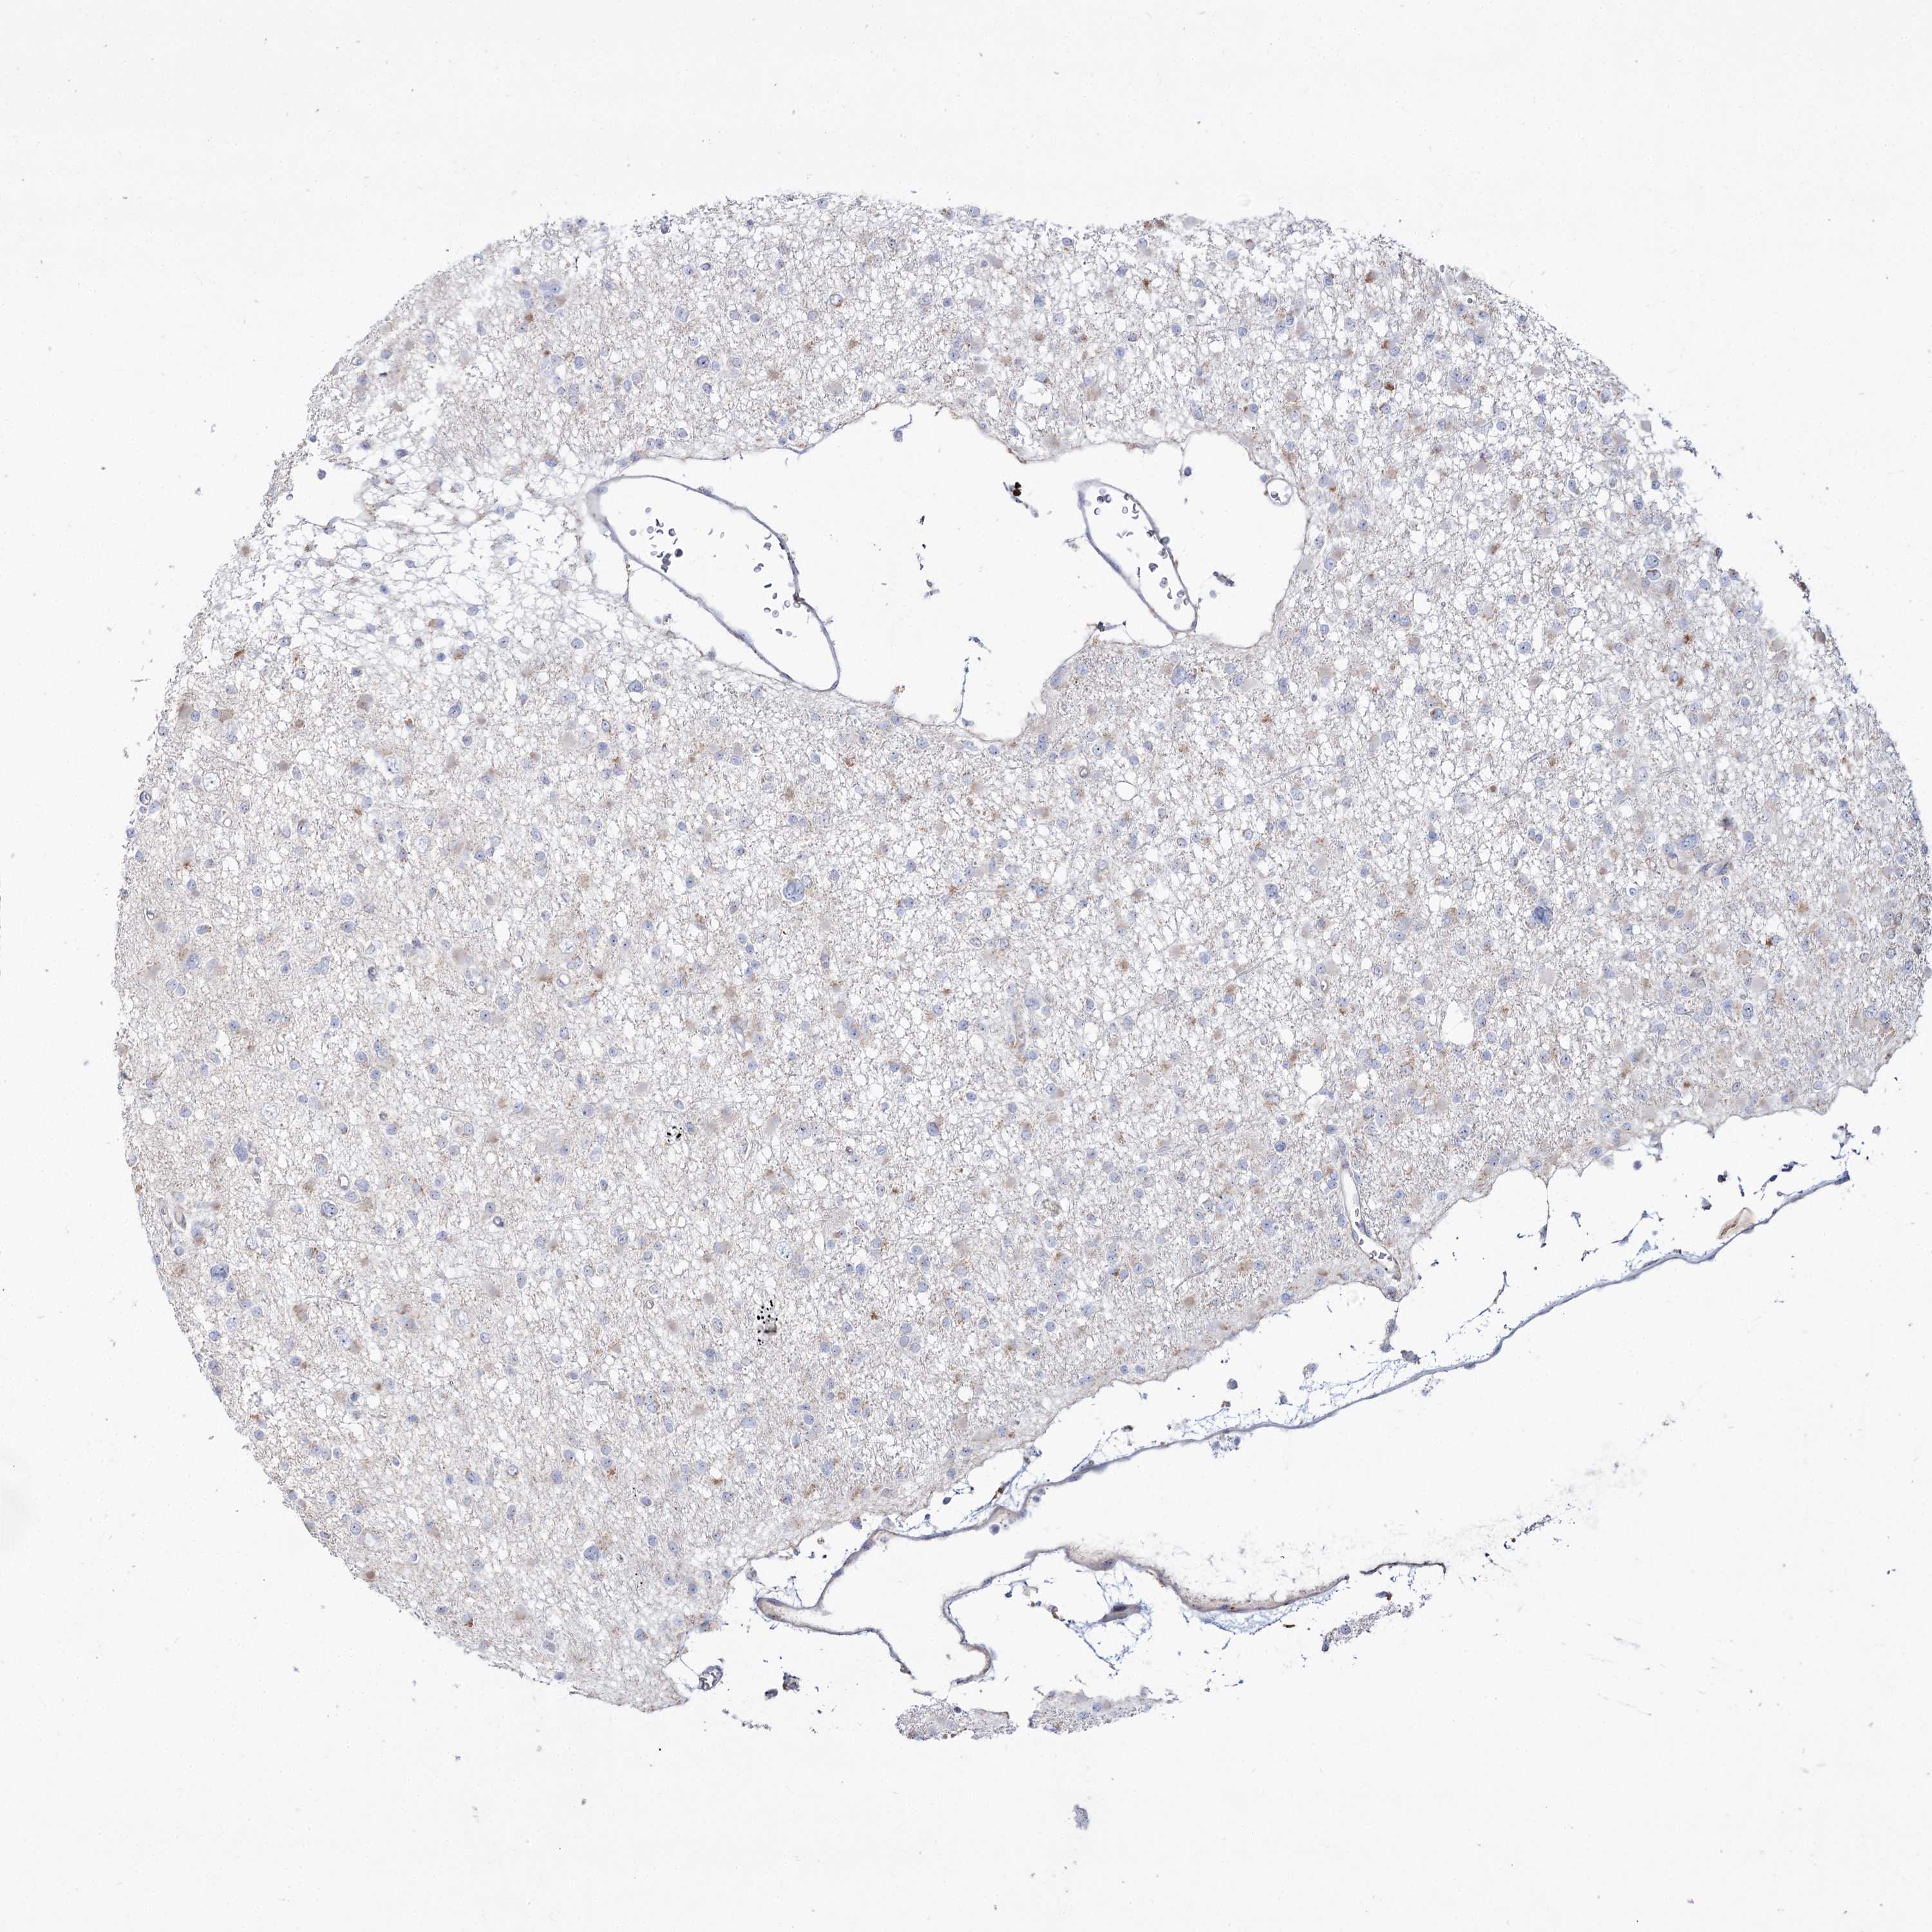

GLIOMA - Protein expressioni

A mouse-over function shows sample information and annotation data. Click on an image to view it in a full screen mode. Samples can be filtered based on level of antibody staining by selecting one or several of the following categories: high, medium, low and not detected. The assay and annotation is described here.

Note that samples used for immunohistochemistry by the Human Protein Atlas do not correspond to samples in the TCGA dataset.

Antibody stainingi

Antibody staining in the annotated cell types in the current human tissue is reported as not detected, low, medium, or high, based on conventional immunohistochemistry profiling in selected tissues. This score is based on the combination of the staining intensity and fraction of stained cells.

Each image is clickable and will lead to virtual microscopy that enables deeper exploration of all samples and also displays staining intensity scores, fraction scores and subcellular localization as well as patient and tissue information for each sample.

Antibody HPA038208

Antibody HPA038209

Staining

High

Medium

Low

Not detected

Intensity

Strong

Moderate

Weak

Negative

Quantity

>75%

75%-25%

<25%

None

Location

Nuclear

Cytoplasmic/membranous

Cytoplasmic/membranous,nuclear

Glioma, malignant, High grade

Glioma, malignant, Low grade

Glioblastoma, NOS